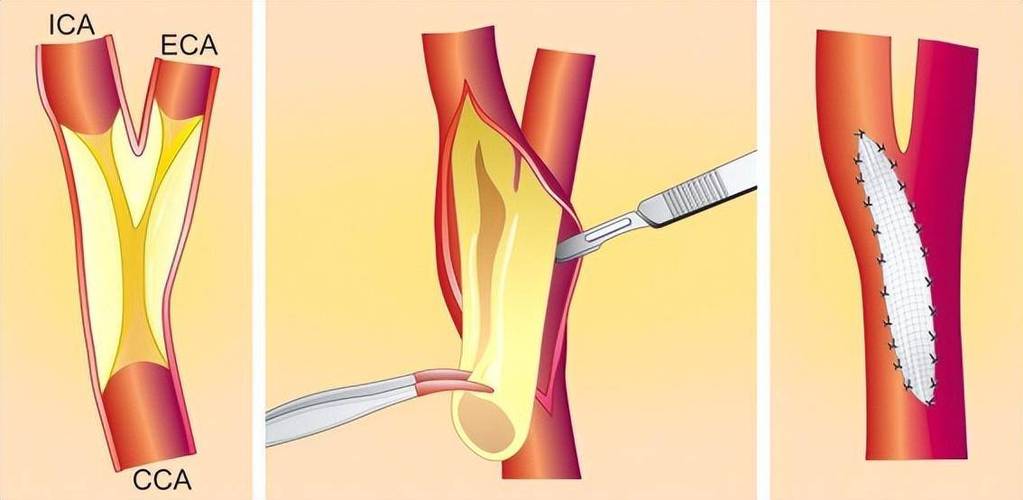

- 手术治疗:对于严重狭窄(狭窄率>70%)或高风险斑块,可能需考虑支架植入或内膜剥脱术。